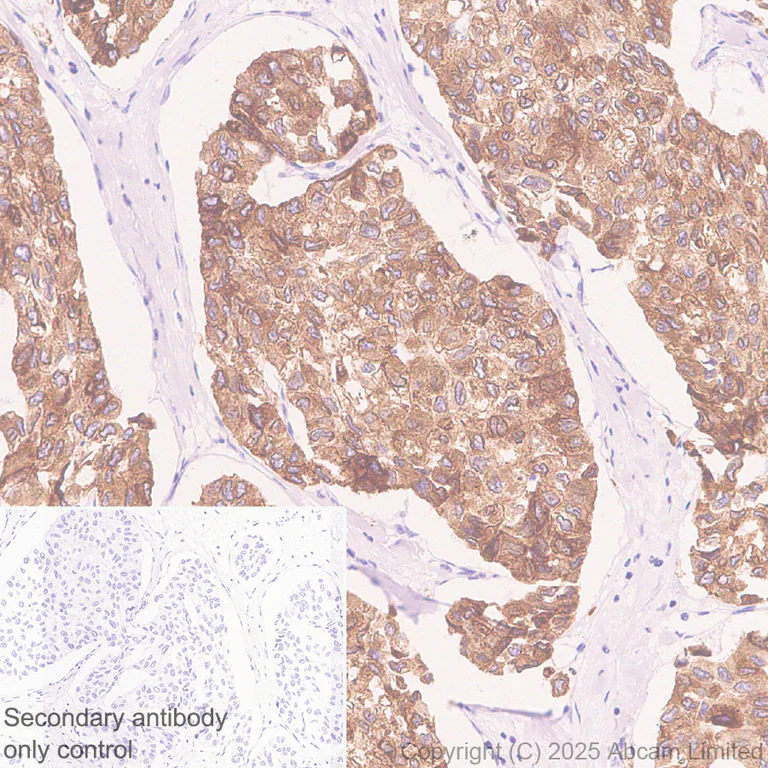

Immunohistochemical analysis of paraffin-embedded Human breast cancer tissue labeling LENG4 with ab325494 at 1/500 (1.066 µg/ml) dilution, followed by a ready to use LeicaDS9800 (Bond™ Polymer Refine Detection).

Cytoplasmic staining on human breast cancer.

The primary antibody was incubated for 30 mins at room temperature.

The immunostaining was performed on a Leica Biosystems BOND® RX instrument.

Counterstained with Hematoxylin.

Secondary antibody only control : Secondary antibody is a ready to use LeicaDS9800 (Bond™ Polymer Refine Detection).

Heat mediated antigen retrieval was performed with Tris-EDTA buffer (pH 9.0, Epitope Retrieval Solution2) for 20 mins